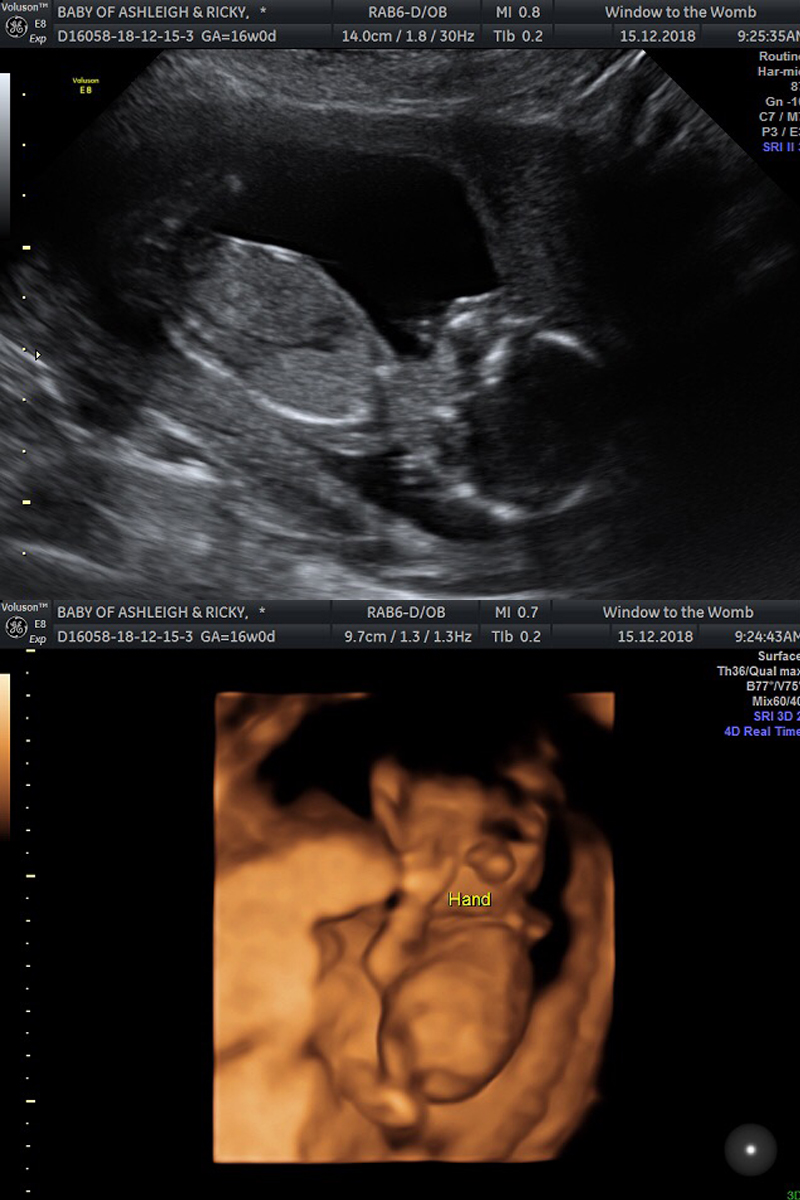

I booked a private scan for Saturday 15th December to find out the sex of our baby. It's such a personal thing whether to find out or not, but Ricky and I both agreed that we can not wait up to 42 weeks and we also wanted to better prepare ourselves with clothes, baby's room etc.

Onto the scan itself incase anyone is interested in reading more about early gender scans. We had ours at 16 weeks.

I cannot recommend Window To The Womb private clinics enough (*not sponsored). You are made to feel welcome and special the moment you walk in and the scan itself is made to be much more special in my opinion. We had the same sonographer as our early 6 week scan, so it was nice to see a familiar face and the setting is super comfortable and relaxing; spa like music and low, warm lighting and a sofa provided for up to 5 guests that you are allowed to bring.

The package we paid for gave us a gender reveal, health check and a sneak preview in 4D - something we was all really looking forward to.

Baby is a little wriggler and kept moving around, mostly standing on this head! However, these two photos are my favourite as you can really see details. In the 4D photo, it sort of looks like a huge nose, but it's actually his two hands on his face. You can see a thumb so clearly!